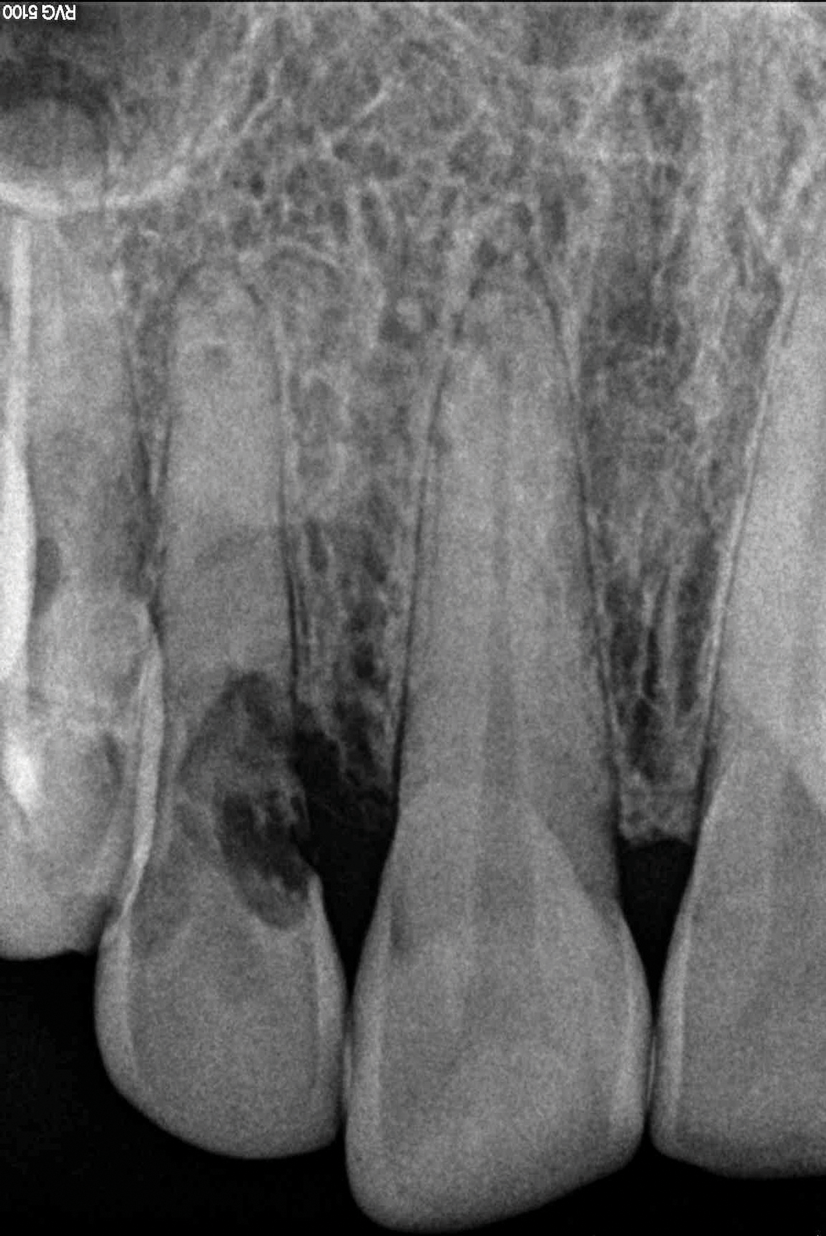

1. Isolate the Operating Field

For any adhesive procedure, optimizing bond strength hinges on achieving proper isolation of the operating field. Placing a rubber dam ensures a pristine and fluid-free field, creating an ideal environment for both bonding and the subsequent development of the resin bridge (Figure 3). Achieving complete isolation is particularly important in cases involving replacement of a missing tooth immediately after extraction or implant placement.

(3.) Placement of a rubber dam to achieve isolation.

Figure 3